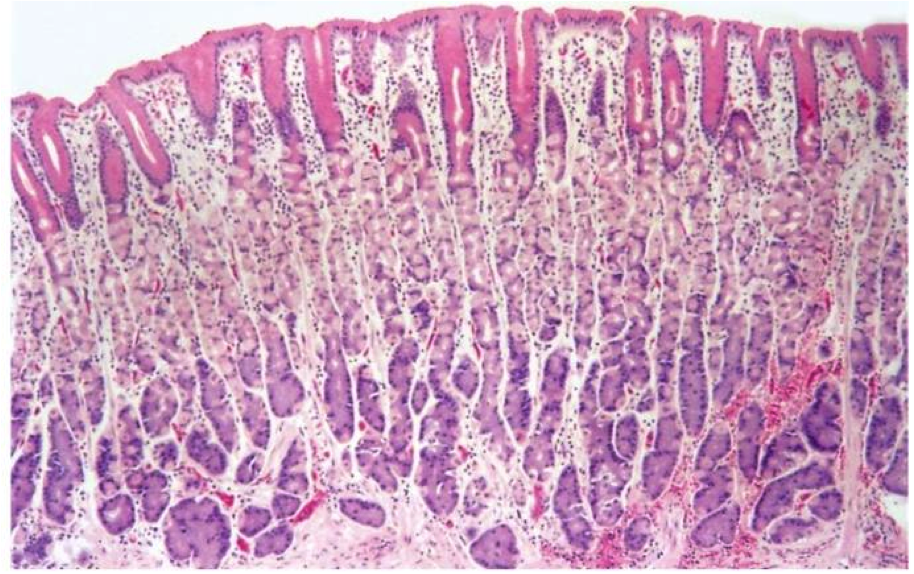

Fundus, body

Parietal (oxyntic) glands

Pink = parietal cell

Blue/purple = chief cell